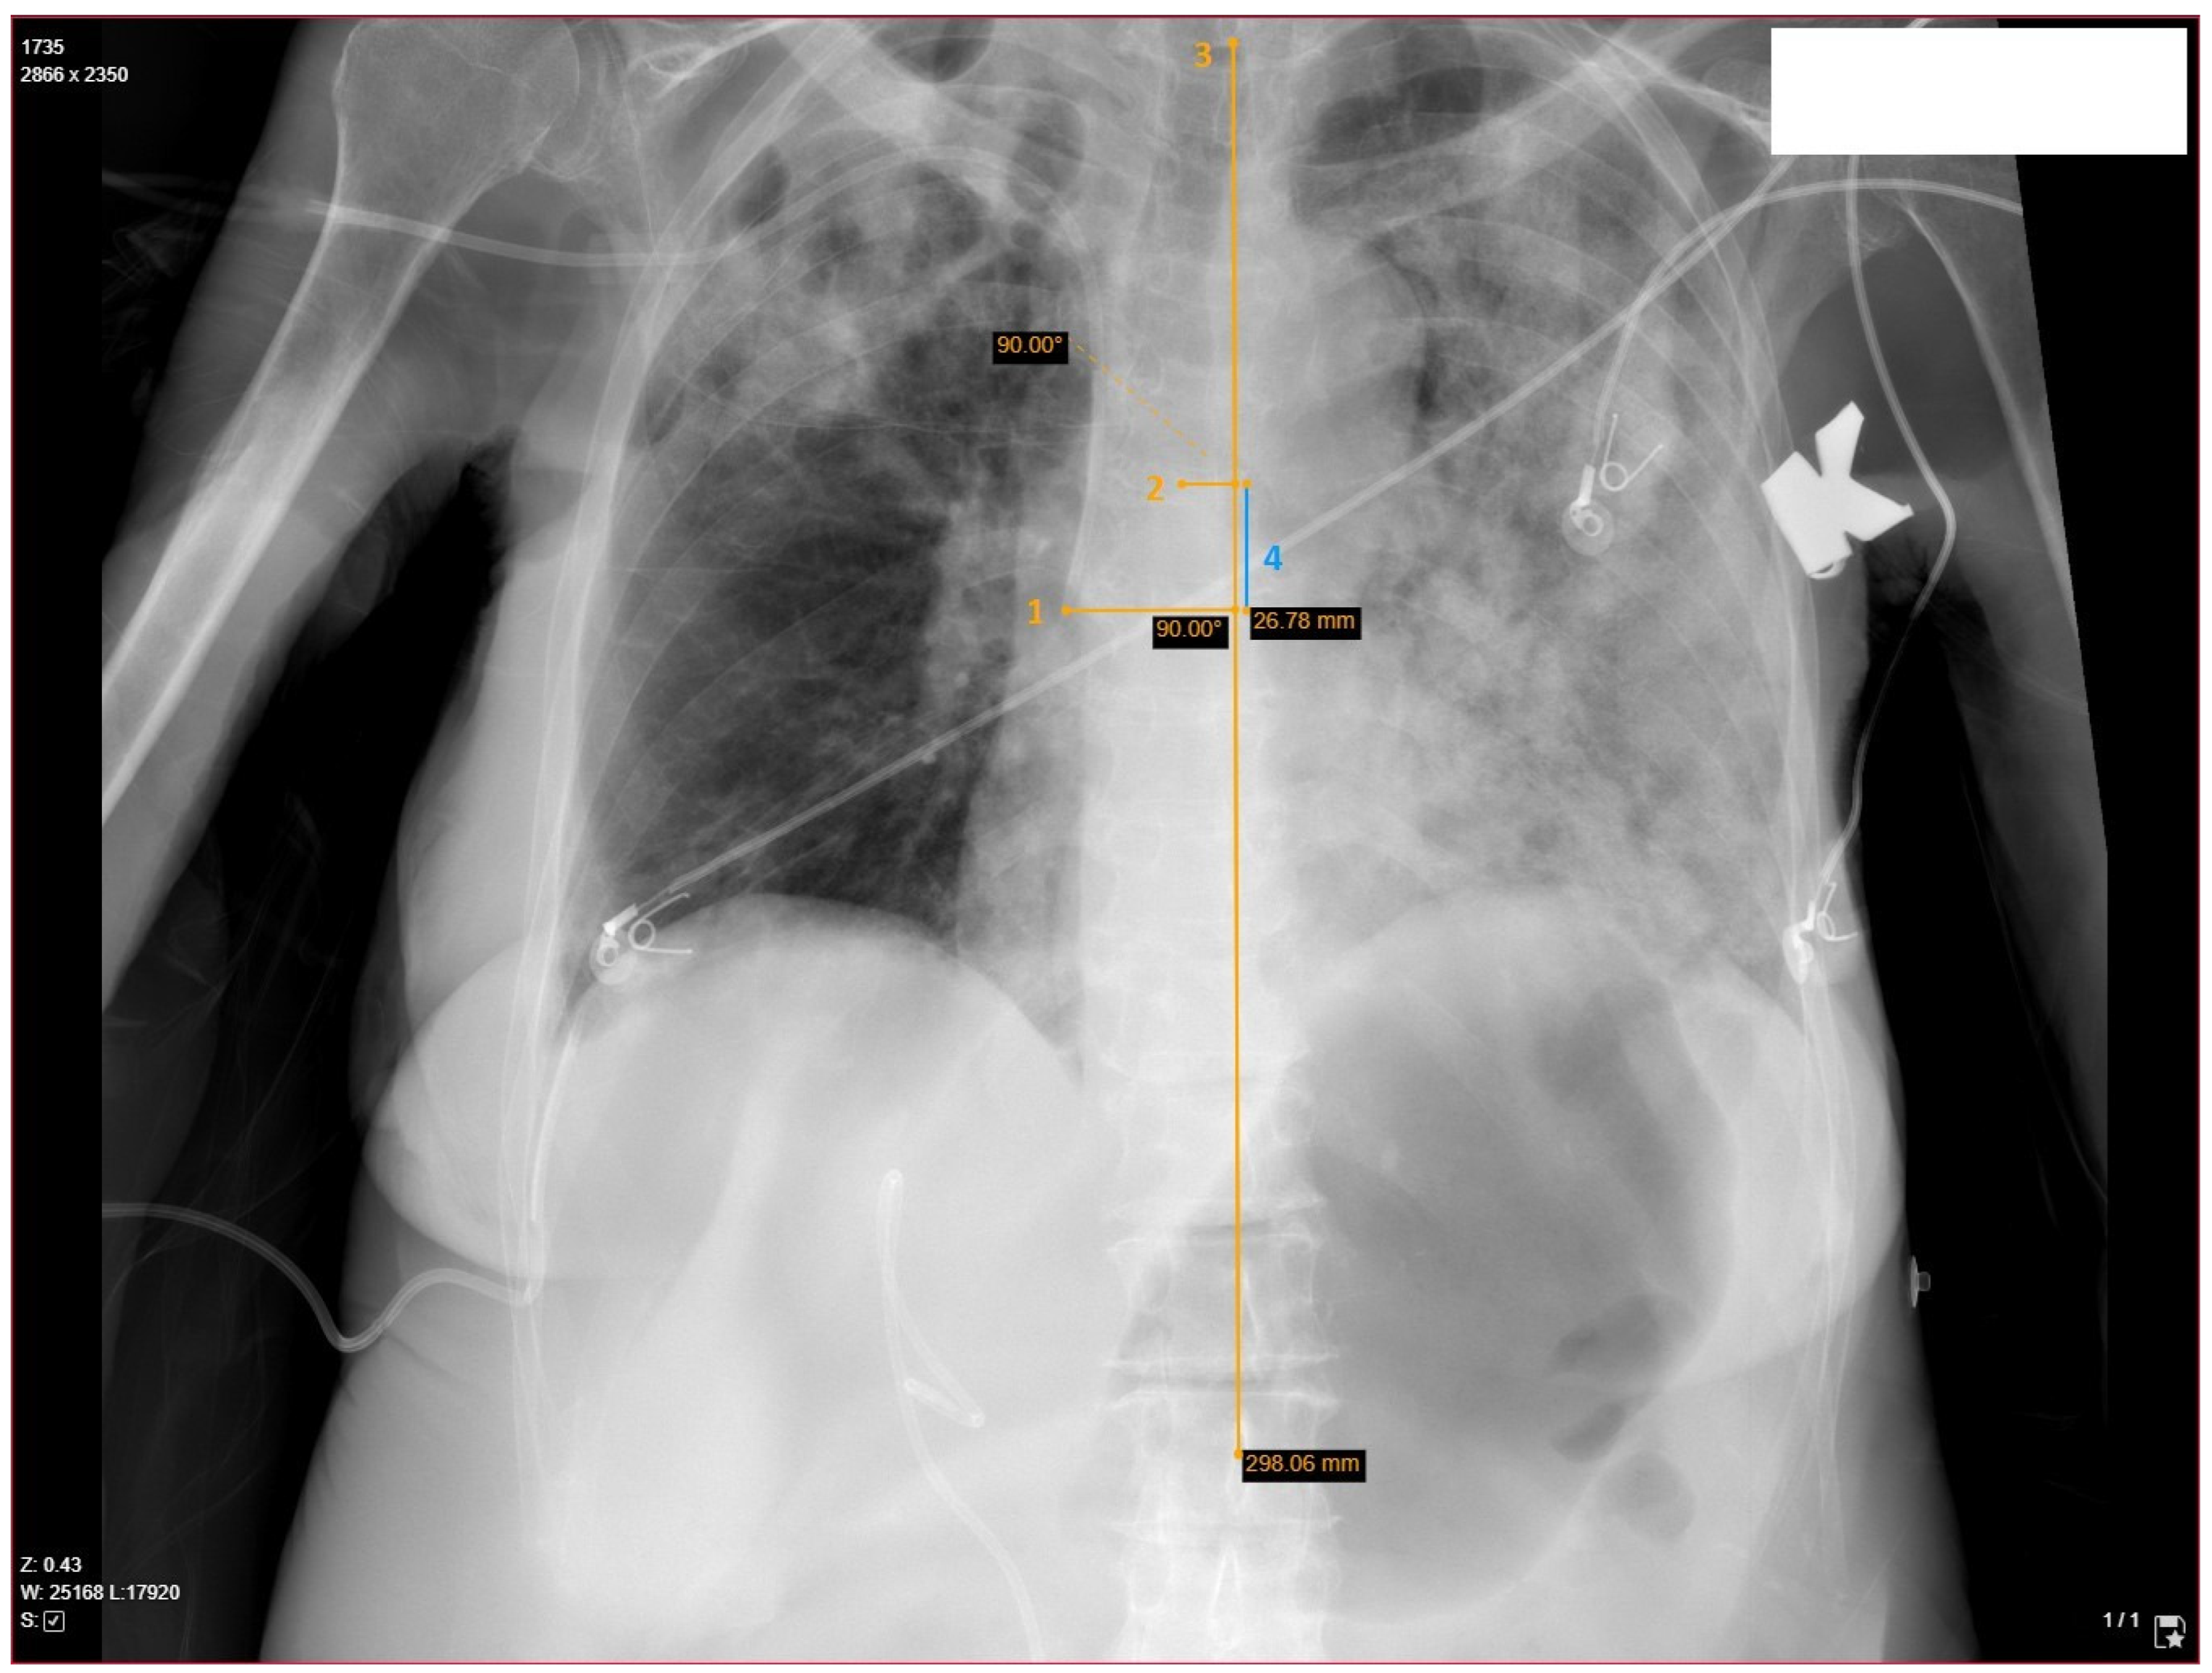

2.3. Determination of Catheter’s Length, Position and Relevant Anatomy